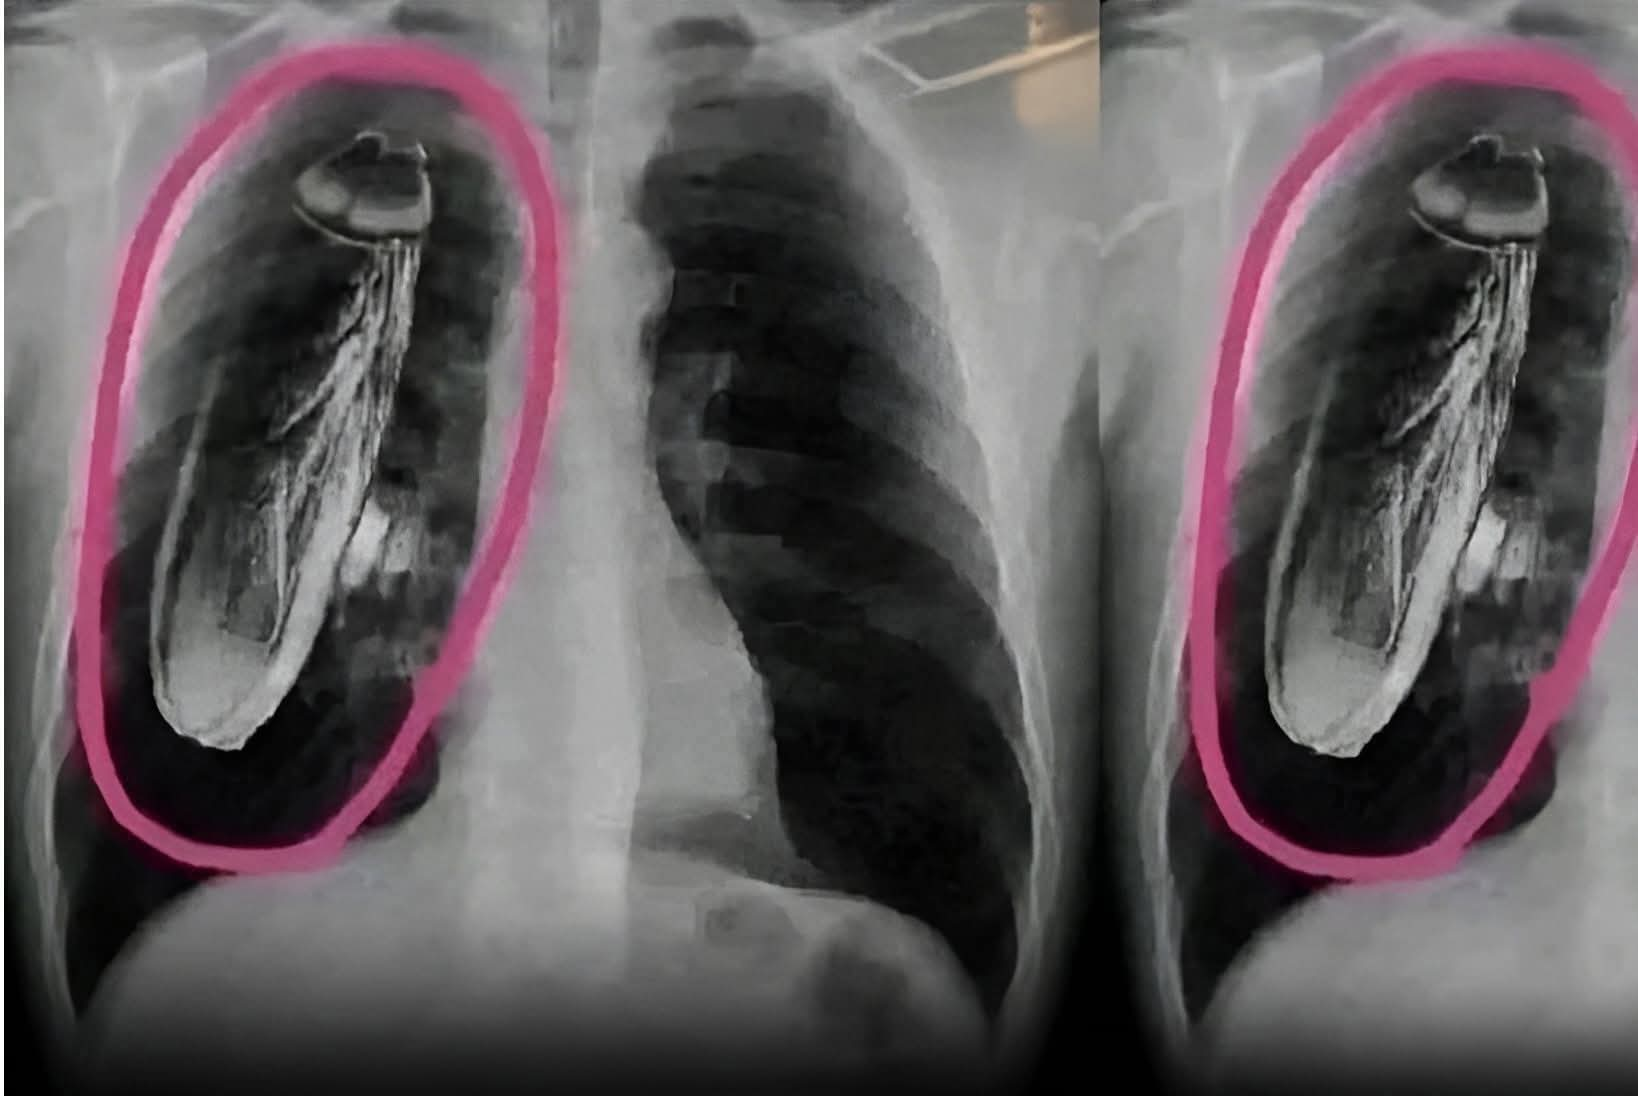

ЁЯШнрдмрджреНрджреА рдореЗ рдЖрдП рдЖрдЬ рд╕рд┐рдВрдЧрд╛рдкреБрд░ рдХреЗ рдПрдХ рдкрд░реНрдпрдЯрдХ рдХреЛ рд╕реАрдиреЗ рдореЗрдВ рджрд░реНрдж рдорд╣рд╕реВрд╕ рд╣реБрдЖ рдФрд░ рдЗрд▓рд╛рдЬ рдХреЗ рд▓рд┐рдП рд╡рд╣рд╛рдВ рд╕рд░рдХрд╛рд░реА рдЕрд╕реНрдкрддрд╛рд▓ рдЧрдпрд╛ред рдбреЙрдХреНрдЯрд░ рдиреЗ рдЕрдкрдиреЗ рдХреБрдЫ рдЯреЗрд╕реНрдЯ рдкрд░ рдПрдХреНрд╕-рд░реЗ рдХрд┐рдпрд╛ рдФрд░ рдХрд╣рд╛ рдХрд┐ рддреБрд░рдВрдд рд╕рд┐рдВрдЧрд╛рдкреБрд░ рд╡рд╛рдкрд╕ рдЗрд▓рд╛рдЬ рдХреЗ рд▓рд┐рдП рдЪрд▓реЗ рдЬрд╛рдУ рдХреНрдпреЛрдВрдХрд┐ рдЙрд╕рдХреЗ рд╕реАрдиреЗ рдореЗрдВ рдЬрд┐рдВрджрд╛ рддрд┐рд▓рдЪрдЯреНрдЯреЗ рд╣реИрдВред рдирд┐рд░реНрджреЗрд╢реЛрдВ рдХреЗ рд╕рд╛рде, рдЖрдкрдХреЛ рдЕрдкрдиреЗ рдлреЗрдлрдбрд╝реЛрдВ рдХреЗ рдЖрдкрд╛рддрдХрд╛рд▓реАрди рдСрдкрд░реЗрд╢рди рд╕реЗ рдЧреБрдЬрд░рдирд╛ рдкрдбрд╝ рд╕рдХрддрд╛ рд╣реИред

рдорд░реАрдЬ рдЕрдЪрд╛рдирдХ рд╣рд╛рде-рдкреИрд░реЛрдВ рдореЗрдВ рдЧрд┐рд░ рдЧрдпрд╛ рдФрд░ рдЬрд▓реНрджреА рдореЗрдВ рд╕рд┐рдВрдЧрд╛рдкреБрд░ рд▓реМрдЯ рдЖрдпрд╛ рдФрд░ рдПрдпрд░рдкреЛрд░реНрдЯ рд╕реЗ рд╕реАрдзреЗ рдЕрд╕реНрдкрддрд╛рд▓ рдЪрд▓рд╛ рдЧрдпрд╛ред рдбреЙрдХреНрдЯрд░ рдиреЗ рдЬрд╛рдВрдЪ рдХрд░рдиреЗ рдХреЗ рдмрд╛рдж рдЙрд╕реЗ рдмрддрд╛рдпрд╛ рдХрд┐ рдХреЙрдХрд░реЛрдЪ рдЙрд╕рдХреА рдЫрд╛рддреА рдореЗрдВ рдирд╣реАрдВ рдмрд▓реНрдХрд┐ рдмрджреНрджреА рдХреЗ рдПрдХ рдЕрд╕реНрдкрддрд╛рд▓ рдХреА рдПрдХреНрд╕рд░реЗ рдорд╢реАрди рдХреЗ рдЕрдВрджрд░ рдерд╛редтЬНя╕П